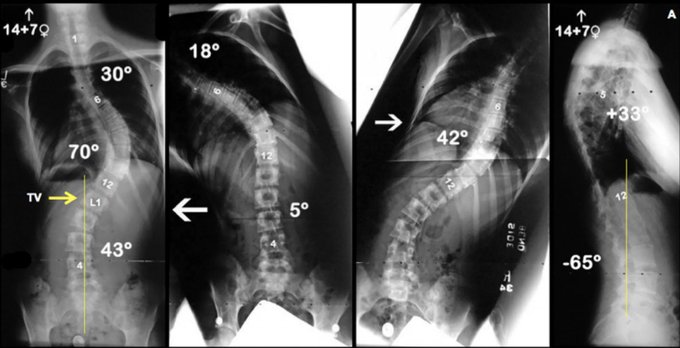

- Desarrollamos un método simple y reproducible para la selección del LIV en pacientes con curvas de Lenke tipo 1 (torácica principal) y 2 (torácica doble) e investigamos su efectividad para producir un posicionamiento óptimo del LIV a los 5 años de seguimiento.

- Recomendamos la regla de «vértebra tocada» (TV) como un tercer modificador en el sistema de clasificación AIS de Lenke. La selección de la «vértebra tocada» (TV) como LIV en pacientes con curvas de Lenke tipo 1 y 2 proporciona una posición aceptable de la LIV en el seguimiento a largo plazo.

- La posición del LIV no fue diferente cuando la fusión se realizó en dirección caudal a la «vértebra tocada» (TV), pero se produjo a expensas de menos segmentos de movimiento.

- Los pacientes con modificador lumbar «A» que se sometieron a fusión cefálica a la «vértebra tocada» (TV) tuvieron una mayor traslación de la LIV, lo que puso a estos pacientes en riesgo de malos resultados a largo plazo.